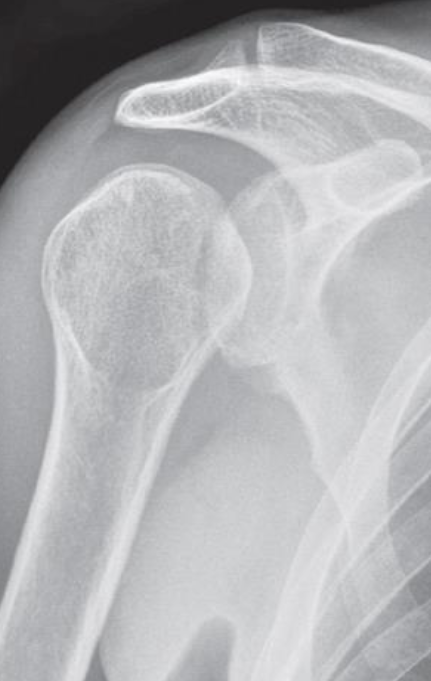

- Plain X-ray

- Electric shock or epileptic seizure

- ‘lightbulb’ appearance of the humeral head.

- Posterior dislocation of the shoulder

Fracture of the neck of the humerus (black arrows)

The greater tuberosity is also fractured (white arrow)